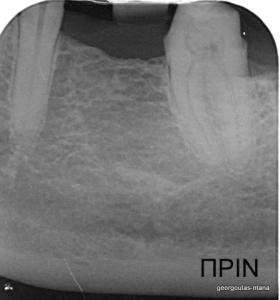

Η ασθενής ήταν δυσαρεστημένη με την αισθητική εμφάνιση των δοντιών της, κυρίως των άνω και κάτω πρόσθιων, τα οποία είχαν εκτεταμένες εμφράξεις σύνθετης ρητίνης που είχαν αποχρωματιστεί. Κάποια από τα οπίσθια δόντια έφεραν κακότεχνες προσθετικές αποκαταστάσεις (γέφυρα, στεφάνες) ενώ κάποια άλλα ήταν τερηδονισμένα. Η ασθενής επιθυμούσε το καλύτερο δυνατό αισθητικό αποτέλεσμα. Για το λόγο αυτό αποφασίστηκε να τοποθετηθούν μεμονωμένες ολοκεραμικές στεφάνες από διπυριτικό λίθιο (Emax) σε όλα τα δόντια της άνω και κάτω γνάθου, ώστε να εξασφαλιστεί το καλύτερο αισθητικό αποτέλεσμα. Χρησιμοποιήθηκε η τεχνική MIPP (Minimally Invasive Prosthetic Procedures) με ελάχιστη αποκοπή οδοντικών ιστών και μονολιθικές αποκαταστάσεις Emax στα οπίσθια δόντια.  Στη θέση του κάτω αριστερού πρώτου γομφίου, ο οποίος έλειπε και είχε αντικατασταθεί με γέφυρα που στηρίζονταν στα διπλανά δόντια, αποφασίστηκε να τοποθετηθεί εμφύτευμα. Σε όλη τη διάρκεια της θεραπείας η ασθενής ήταν καλυμμένη με προσωρινές προσθετικές αποκαταστάσεις.